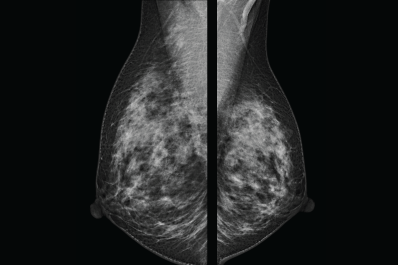

La mastografía es una radiografía especial de las glándulas mamarias cuyo objetivo principal es detectar el cáncer temprano de la mama.

Se realiza con equipo y películas radiográficas diseñados exclusivamente para este propósito.

Se pueden tomar al menos dos radiografías de cada seno desde las posiciones superior y lateral para producir las placas a fin de que el médico las revise.